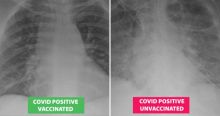

Mengerikan, Hasil Sinar-X Menunjukkan Bagaimana Covid-19 Merusak Paru-paru Pasien yang Tidak Divaksinasi Kesehatan - 06 Aug 2021, 15:22